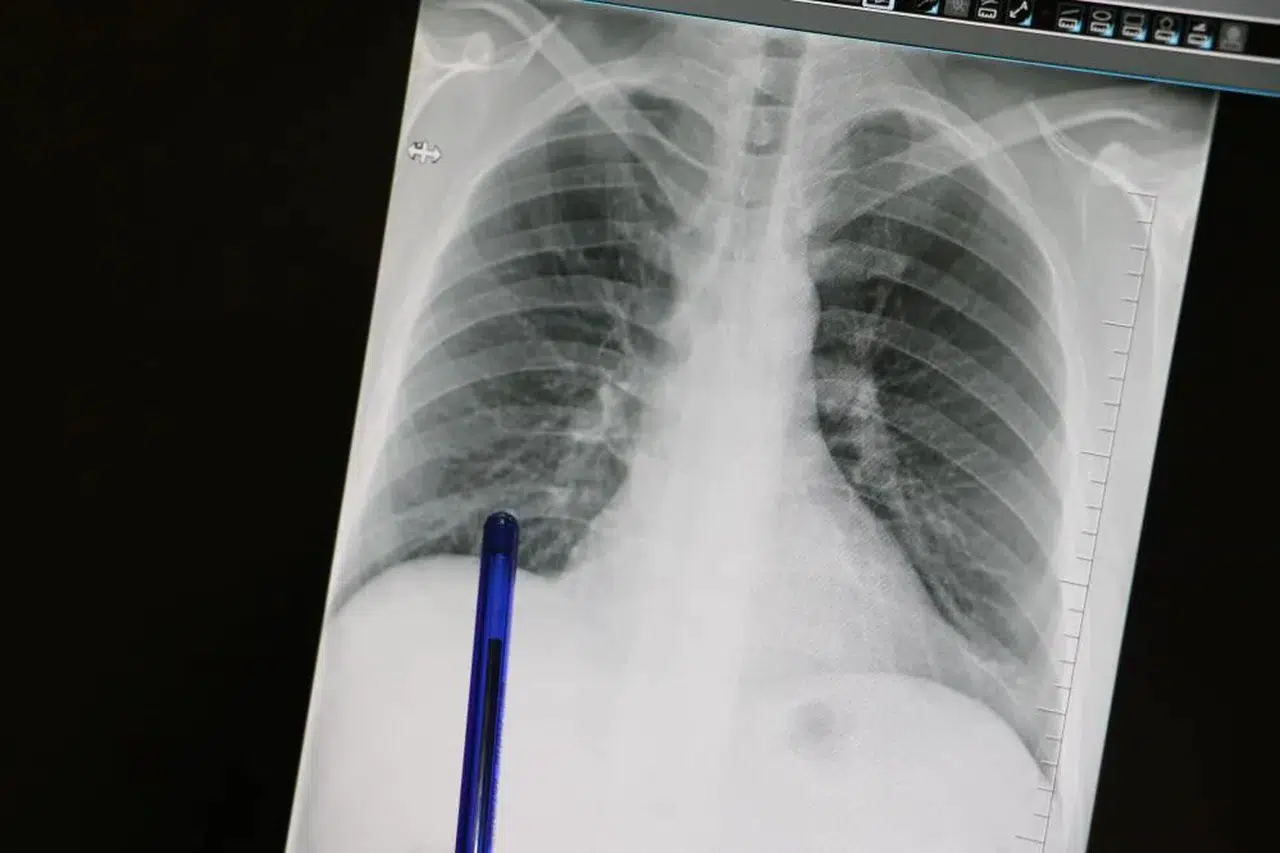

Kasım ayı, Türkiye’de ve dünyada hayati bir konuya dikkat çekiyor: Akciğer Kanseri Farkındalık Ayı. Akciğer dokusundaki hücrelerin kontrolsüz çoğalmasıyla ortaya çıkan ve tüm kansere bağlı ölümlerin en sık nedeni olan bu sinsi hastalık, basit görünen semptomların arkasına gizlenebiliyor.

Medicana Sivas Hastanesi Göğüs Hastalıkları Uzmanı Dr. Büşra Yayla Yerlikaya, pek çok kişinin önemsemediği öksürük ve balgam gibi belirtilerin, ne yazık ki akciğer kanserinin ilk habercisi olabileceğini vurguladı. Dr. Yerlikaya, "Bu hastalık, ne yazık ki genellikle erken evrede belirti vermediği için geç tanı alabilmekte ve bu da tedavi şansının azalmasına sebep olabilmektedir," uyarısında bulundu.

Hastalık Sinsice İlerliyor: Erken Evrede Belirti Vermiyor